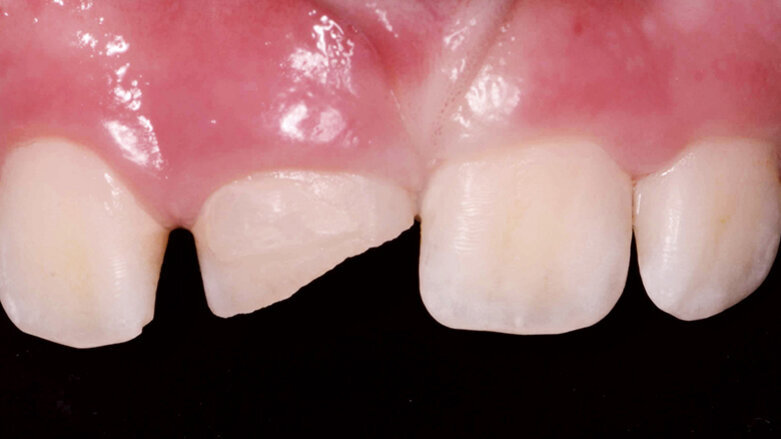

Při klinickém vyšetření nacházíme sanovaný smíšený chrup odpovídající věku pacienta. Zub 11 je poklepově a palpačně nebolestivý, parodontální sondáž je v mezích fyziologické normy. Z vestibulárního pohledu tvarově a velikostně odpovídá kontralaterálnímu zubu (obr. 1), z okluzního pohledu je vestibuloorální rozměr nepatrně větší než u zubu 21 (obr. 2). Šikmá fraktura zubu 11 má meziální okraj cca 1 mm nad okrajem marginální gingivy a distálně zasahuje do incizální třetiny klinické korunky. Dle diagnostického intraorálního rentgenového snímku je ukončen vývoj kořene s přítomným periapikálním nálezem a projasněním na meziálním aspektu kořene. Na ortoradiálním intraorálním rentgenovém snímku, ve srovnání se zubem 21 není jasně zřetelný průběh kořenového kanálku (obr. 3) a na excentrickém rentgenovém snímku je viditelný náznak kontury druhého kořene (obr. 4).